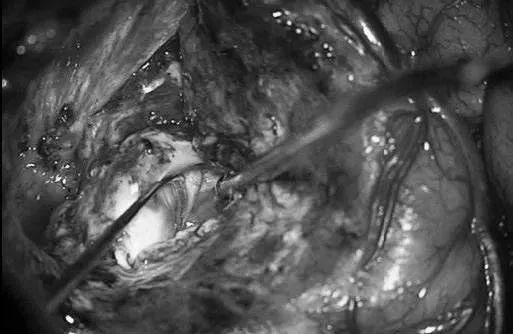

Lawton教授手术操作情况

▼左侧翼点开颅,再次手术,显露前颞叶。

▼沿颞下回经原皮层入路达颞角。

▼AChA经脉络裂进入颞角,在前方供应AVM,lPChA在后方供应AVM。

▼通过ITG经皮层显露可以充分显露颞角,达到全切AVM。